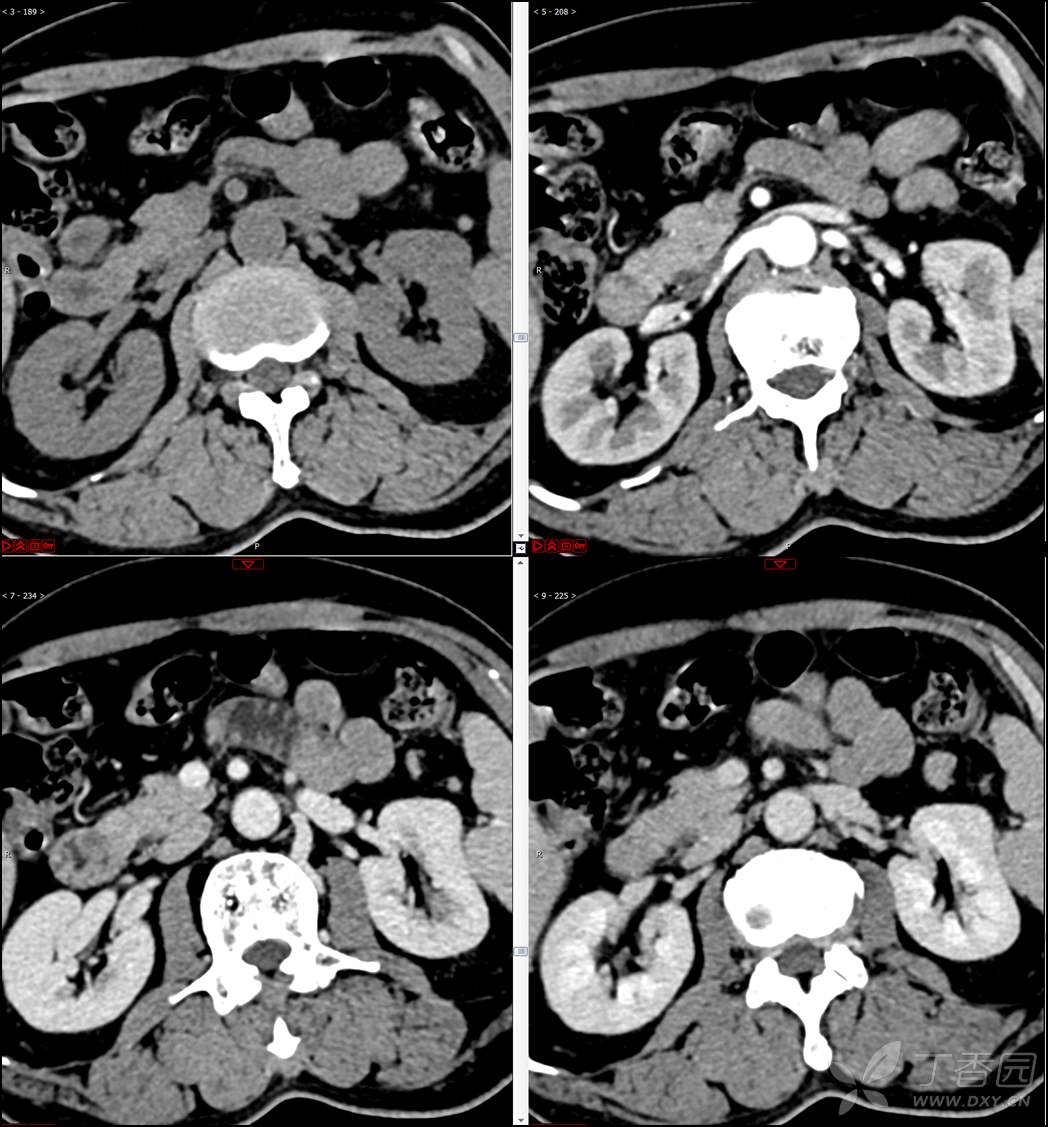

【影诊笔记521】老年男性,黑便就诊,请分析~『回帖即可查阅答案』

患者年龄:67岁

主诉:黑便1周。

现病史:患者1周前无明显诱因出现黑便伴头晕、心慌,无胸闷、胸痛,后仍间断黑便,2022-10-27就诊于某市中医院,行胃镜检查示:十二指肠溃疡伴出血,给予止血、抑酸等对症治疗,效果欠佳。今为行进一步治疗就诊于我院急诊,门诊完善新型冠状病毒核酸检测后以“十二指肠溃疡伴出血”收入我科。患者自发病以来,神志清,精神可,未进食,睡眠可,小便未见异常,黑便,近期体重无明显增减。